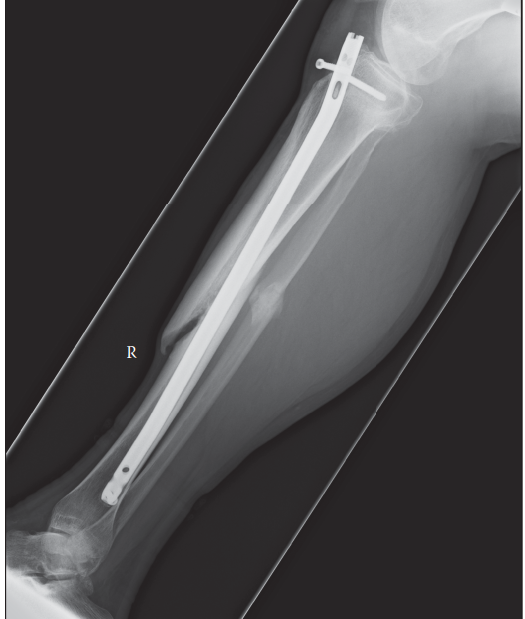

s 1 year down the line following an open fracture of the tibia treated with an intramedullary nail. 1. Descri…